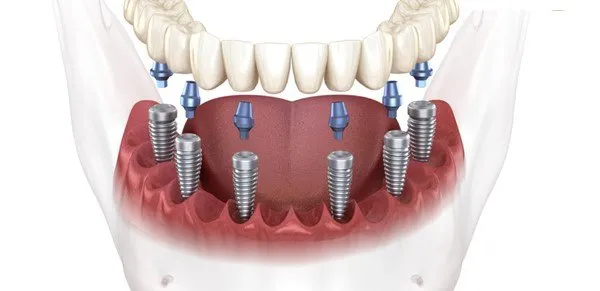

Phục hình răng sứ trên Implant được chỉ định trong các trường hợp mất răng một chiếc hoặc toàn hàm. Phương pháp này hiện rất phổ biến

Phục hình răng sứ trên Implant là phương pháp nha khoa khá phức tạp, đòi hỏi thực hiện bởi nha sĩ tay nghề cao và cơ sở